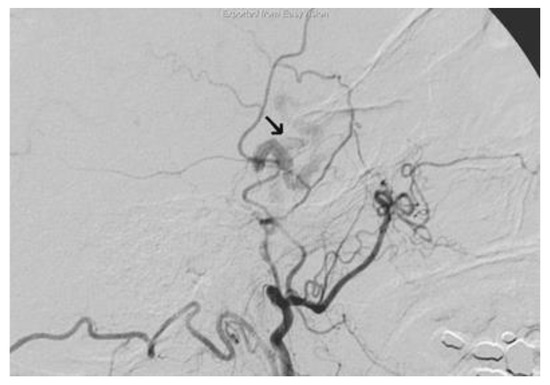

The selective cerebral angiography (Figure 5), carried out through right femoral catheterization, revealed a dural fistula of the right cavernous sinus wall between the branches of the internal maxillary artery, most likely of the accessory meningeal artery, and the cavernous sinus with early opacification of the ophthalmic vein that presented an increased caliber.

The multidisciplinary team involved in this case comprised neurosurgeons and interventional neuroradiologists. The treatment decided was carried out two times; the first provided the insertion of a cannula needle in the right orbital vein by a trans-palpebral anterior approach, while the second provided for the embolization of the cavernous sinus seat of the venous part of the fistula, through the placement of 5 spirals (Vortex 2x5, Boston), up to the complete exclusion of the fistula. The angiographic control performed immediately after the affixing of the spirals showed the complete normalization of the circulation between the internal and external carotid (Figure 6).

Figure 5. The selective cerebral angiography revealing a dural fistula of the right cavernous sinus (arrow).